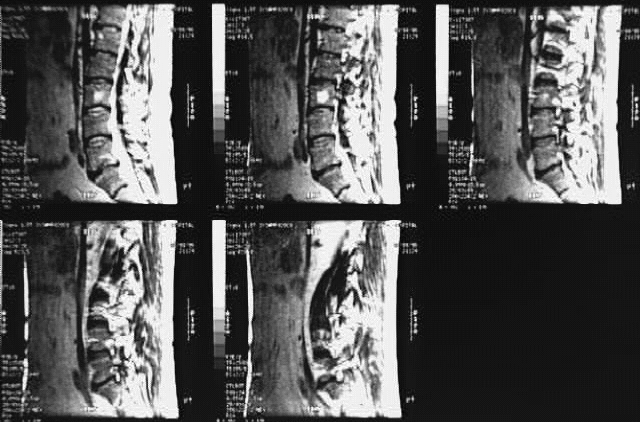

Radiology Images

Back- Lumbar Spine MRI Sagittal 2